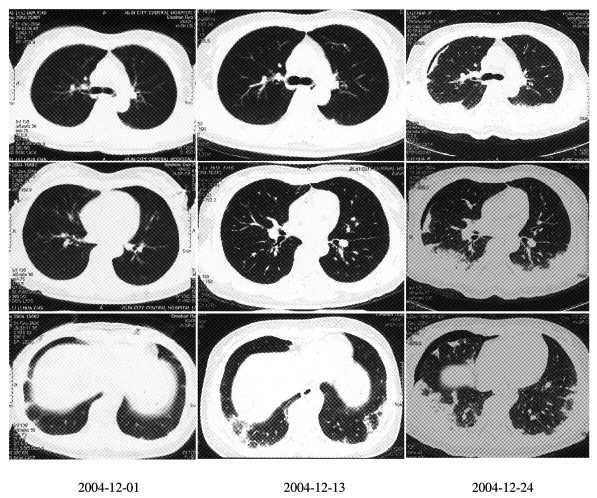

胰腺神经内分泌肿瘤、肺转移性腺癌、肺梗死1例